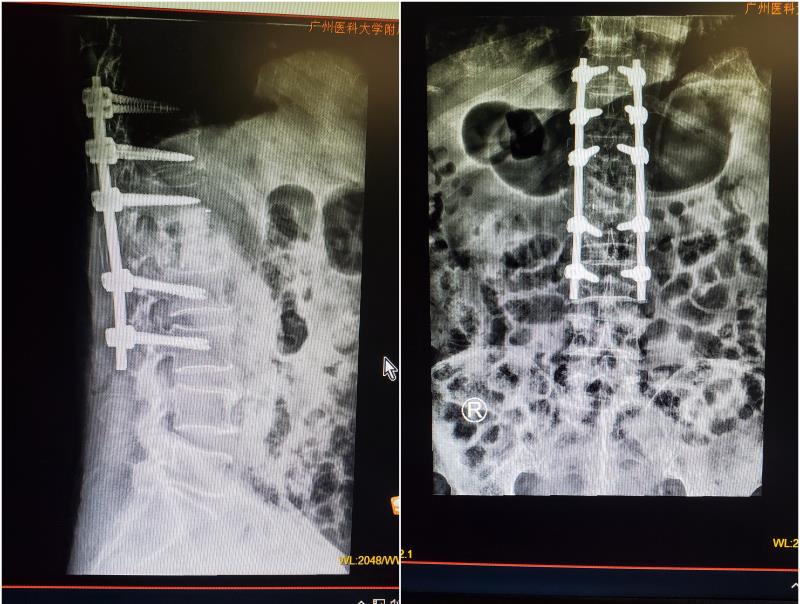

术后成功清除脊椎结核病灶,并重建脊柱稳定性

手术必须尽快完成,但手术的难度也不小。由于结核病菌的侵蚀,张老伯的第1腰椎椎体已经出现压缩塌陷、并压迫了椎管神经,手术需要在保护好脊髓和神经的前提下,切除病变的椎体;这个操作本身就存在非常高的神经损伤风险。与此同时,病灶的清除也需要十分彻底,否则残余的病灶还可能迁延到其他部位,这需要医者在术中非常仔细。把病变椎体切除后,脊柱的稳定性需要重建,这就需要使用合适大小的椎间支撑体及螺钉辅助固定,若对植入物选材不当还会增加手术远期失败及二次手术的风险。手术的风险和难度不小,如果因技术问题不慎伤及神经导致瘫痪,这对于病人来说无疑是灾难性的。

术前,吴增晖教授团队进行了周密的术前规划,9月10日,骨科吴增晖教授主刀,采用了先进的超声骨刀和其他精密的脊柱手术器械,历时近5个小时,顺利为老伯清除脊柱结核病灶,并重建脊柱。